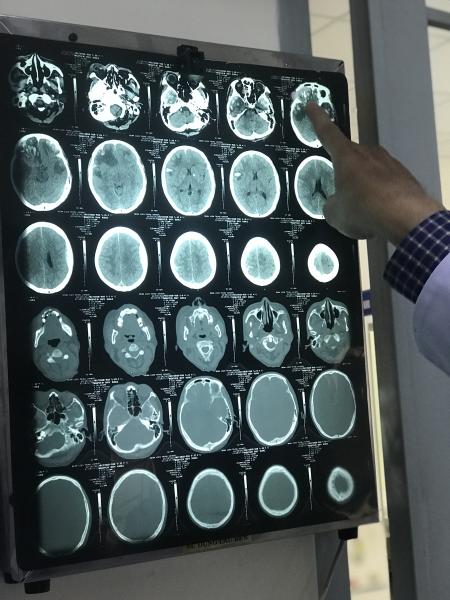

Bệnh nhân là cư dân huyện Cẩm Mỹ, tỉnh Đồng Nai nhưng làm việc tại tỉnh Bà Rịa - Vũng Tàu. Sau tại nạn khiến gần như toàn bộ sọ não bị chấn thương nặng như dập não trán 2 bên, máu tụ ngoài màng cứng, vỡ sàn sọ trước làm bầm tím 2 mắt, ngoài ra còn có chấn thương chân khá nặng. Theo thân nhân, bệnh nhân được đưa vào cấp cứu tại bệnh viện thành phố Vũng Tàu và bệnh viện tỉnh Bà Rịa - Vũng Tàu. Tuy nhiên, cả 2 bệnh viện đều cho biết chấn thương quá nặng, mọi can thiệp hay ngay cả việc chuyển viện đều có thể đe doạ đến tính mạng. Gia đình đã đưa về lo hậu sự nhưng thấy tình trạng bệnh nhân có khả quan nên đã chuyển lên bệnh viện Trưng Vương, TP. HCM.

Bác sĩ chuyên khoa 2, Nguyễn Hiền Nhân, Khoa Ngoại thần kinh sọ não và cột sống, bệnh viện Trưng Vương, TP. HCM cho biết: bệnh nhân vào cấp cứu trong tình trạng hôn mê. Ê kíp cấp cứu của bệnh viện đã nỗ lực bằng mọi cách để giành lại sự sống cho bệnh nhân. Bệnh nhân được theo dõi sát, điều trị hoàn toàn bằng thuốc, xử lý từng triệu chứng liên tục. Bệnh nhân có dấu hiệu sự sống và ổn định sinh hiệu sau vài ngày. Điều đáng nói là bệnh nhân không có bảo hiểm y tế, nhưng bệnh viện Trưng Vương đã bỏ qua các thủ tục, tập trung cứu sống bệnh nhân trước.